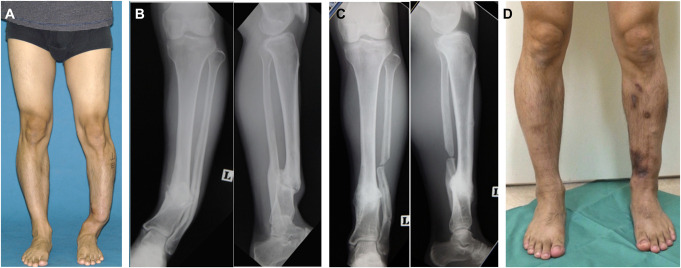

在世界各地,开放性骨折仍然是一个具有挑战性的临床问题,日本也不例外。外科医生在治疗这些损伤的整个过程中都面临着关键的决定,这些决定可能会对临床结果产生重大影响,包括抗生素用药的类型和时机、固定、软组织处理以及骨折后并发症的干预等。2022 年 10 月,日本骨折修复学会(JSFR)应邀作为主宾国学会代表日本参加了在佛罗里达州坦帕市举行的第 38 届创伤骨科学会年会。日本开放性骨折修复协会组织了一场题为 "开放性骨折及相关并发症的治疗--日本的方法 "的研讨会,会上介绍了日本治疗开放性骨折的前沿方法,包括 "固定-翻瓣 "法、局部抗生素灌注法和刺激骨愈合的 "削骨 "法。本文总结了研讨会上这 3 个演讲的内容。

Open fractures continue to be a challenging clinical problem throughout the world, and Japan is no exception. Surgeons are faced with critical decisions throughout the care of these injuries that can have significant effects in clinical outcome, ranging from the type and timing of antibiotic administration, fixation, soft-tissue management, and interventions for postfracture complications. In October 2022, the Japanese Society for Fracture Repair (JSFR) was invited to represent Japan as the Guest Nation society at the 38th Annual Meeting of the Orthopaedic Trauma Society held in Tampa, Florida. The JSFR organized a symposium, entitled "Management of Open Fracture and related complications-the Japanese way," that featured cutting-edge approaches to open fractures in their country, including presentations on the "fix-and-flap" approach, local antibiotics perfusion delivery, and a "chipping" method for the stimulation of bone healing. This article summarizes the content of these 3 presentations from that symposium.